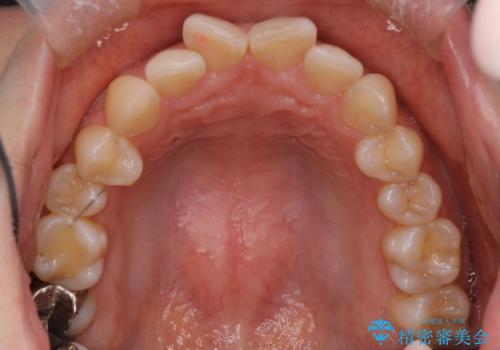

- 前歯の翼状捻転の改善を希望してこられた患者様です。

下顎の叢生はインビザラインで解決することがきましたが、上顎の捻転が完全には改善できなかったため、上顎は途中からワイヤーを用いて治療を行っています。

捻転の改善はインビザラインで苦手とするところですので、うまく治らない場合はワイヤーを提案しています。